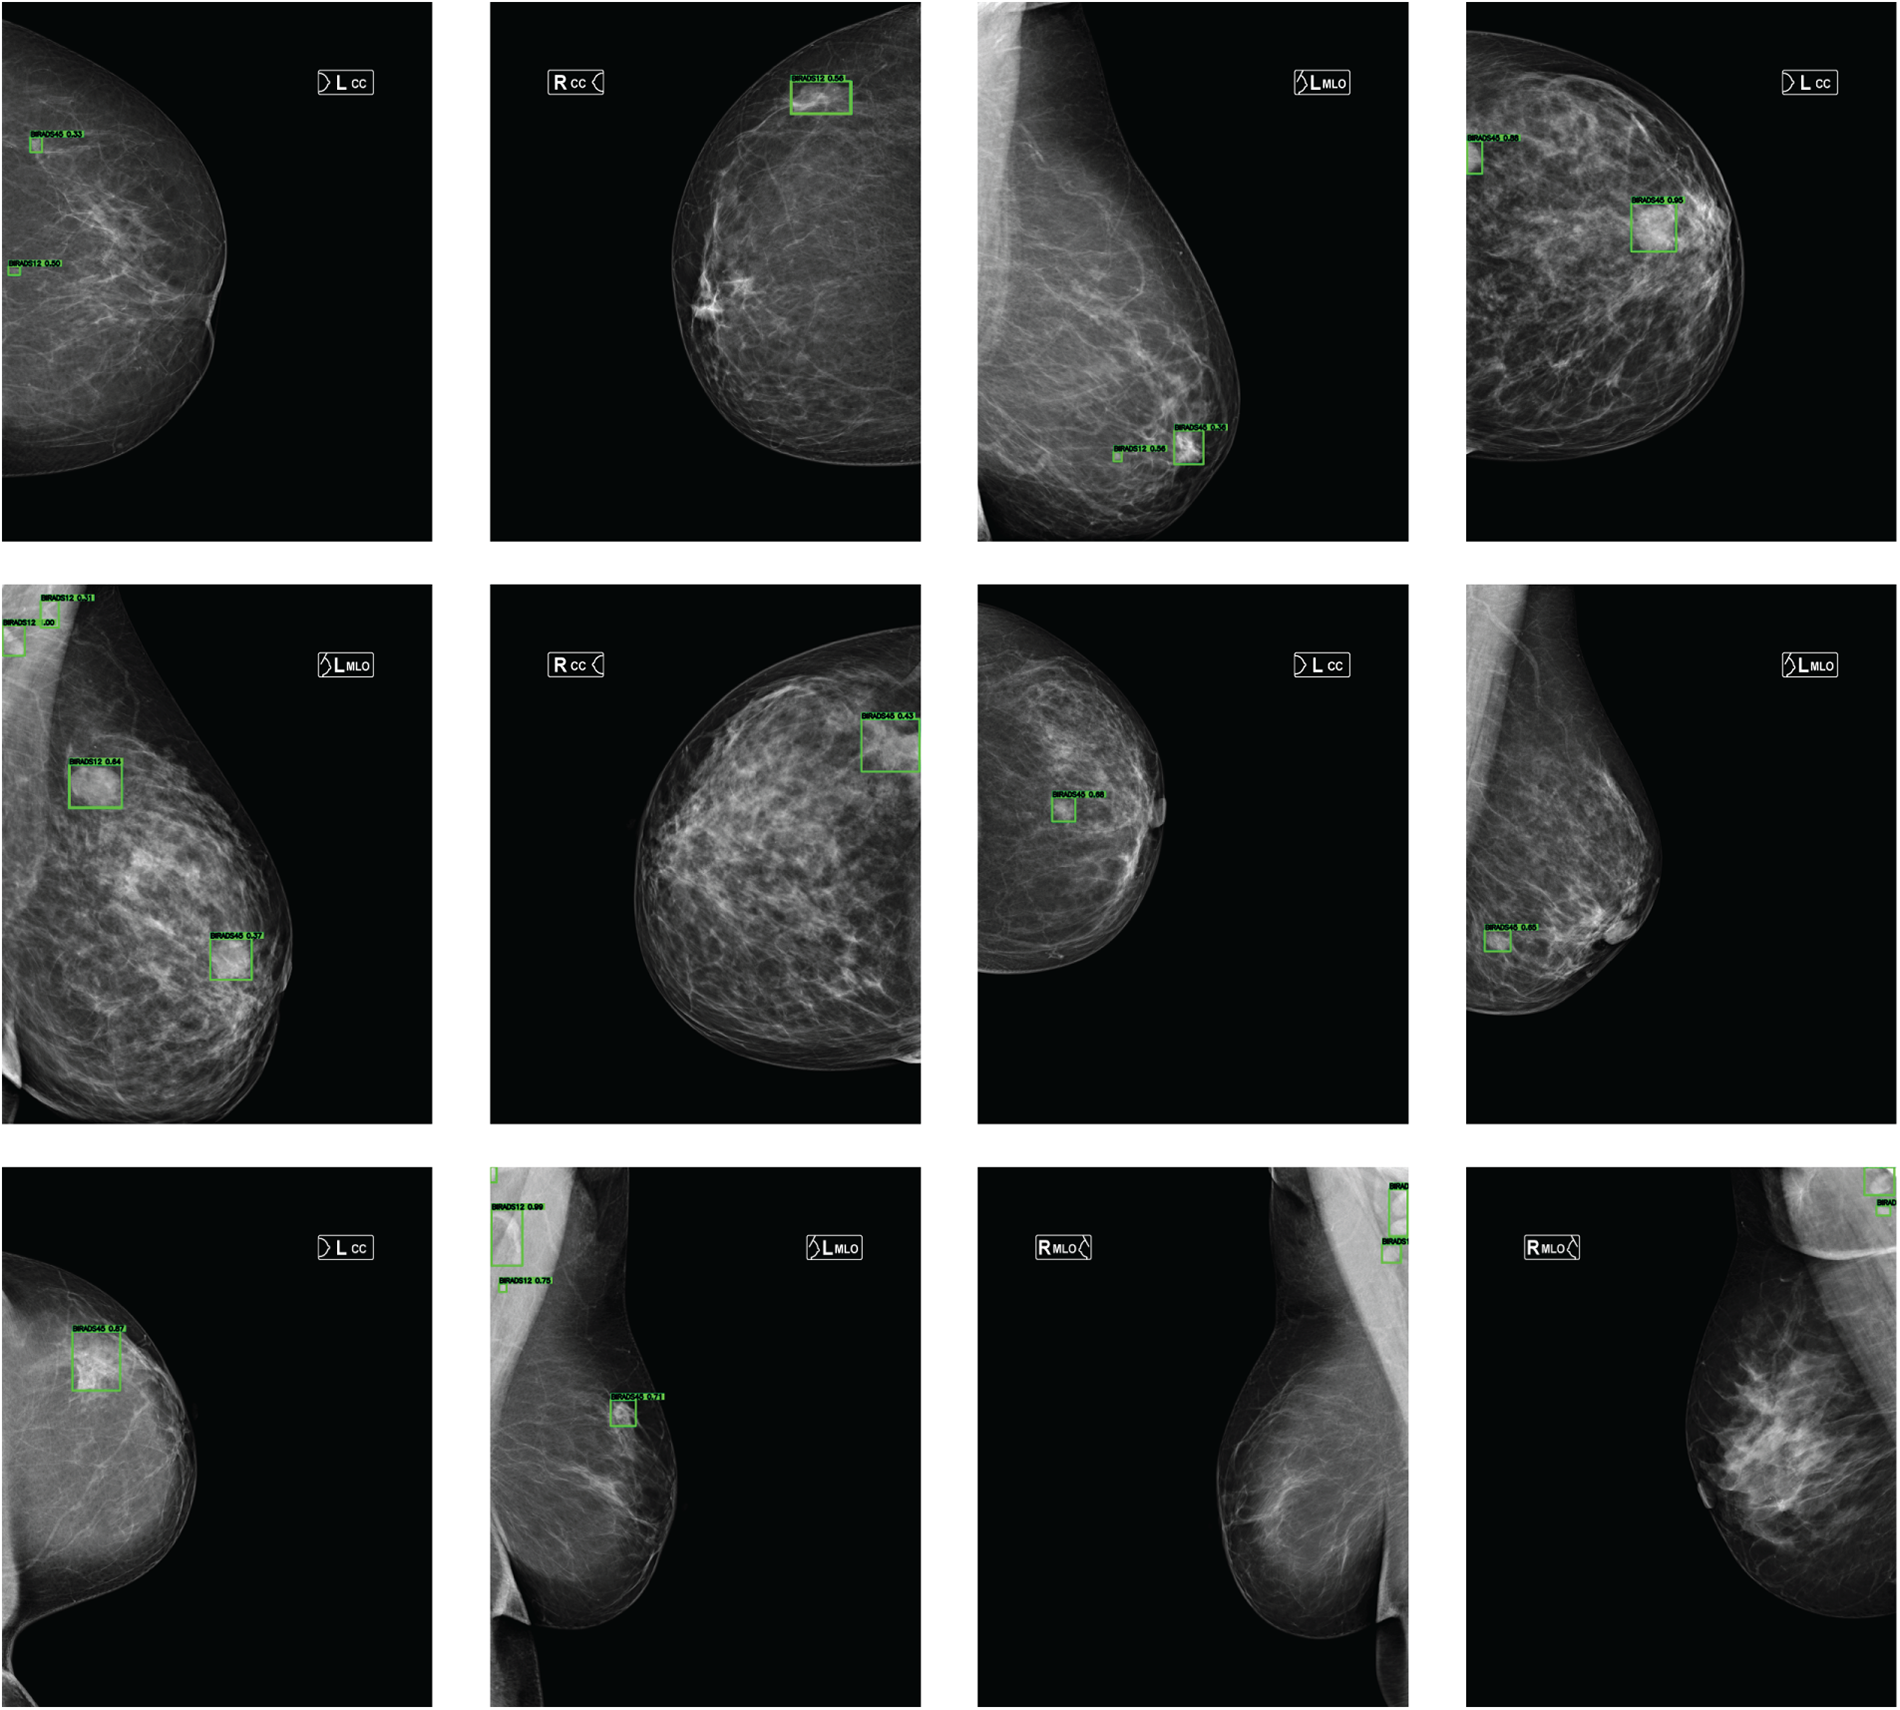

Fig. 3 presents represe + ntative detection examples obtained from mammograms of different patients. The Double-Head R-CNN successfully localizes lesion regions across both low- and high-density breast tissues, demonstrating consistent detection behavior under varying anatomical conditions.

Figure 3: Lesion detection examples on mammograms from different patients in the MammosighTR dataset. Detected regions are highlighted with green bounding boxes